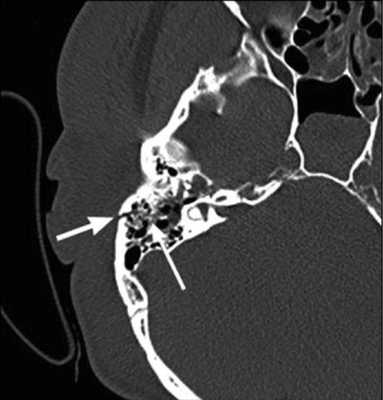

На КТ-снимке виден перелом пирамиды височной кости (указан стрелками)

Шваннома лицевого нерва: осевое КТ-изображение (костное окно) демонстрирует расширение ганглия, присутствует однородная масса мягких тканей (стрелка)

Хроническое воспаление среднего уха с холестеатомой: коронарная КТ показывает боковой свищ полукруглого канала (стрелка), вызванный эрозией кости из-за роста новообразования

Хроническое воспаление среднего уха: осевая КТ демонстрирует очаговую кальцификацию (стрелка) в барабанной полости - тимпаносклероз.